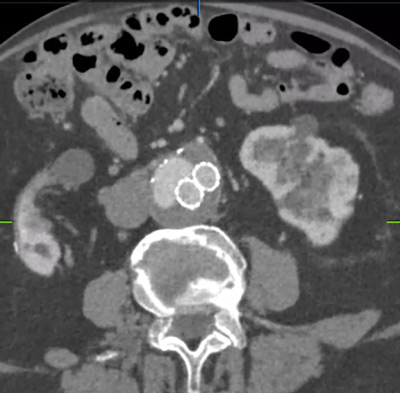

On angio-CT 2024: persistence of EL2, with sac growth (59 mm).

- Sac growth.

- Correct sealing.

- Endoleak lateralised to cava

- Right common femoral vein puncture (TCE)

- Left common femoral artery (control arteriograms)

- Left internal saphenous vein (IVUS guidance)